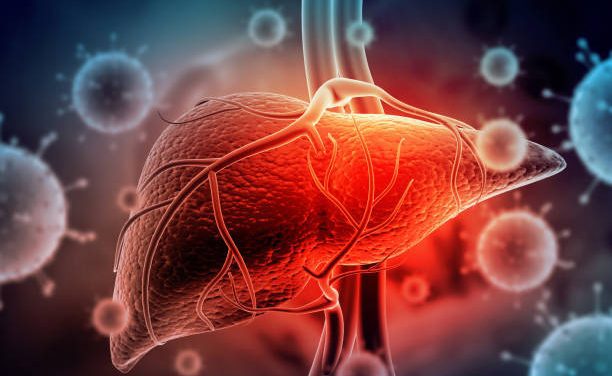

by Kimberly Allen, RN The liver is the main organ in your body responsible for removing toxins...

by Kimberly Allen, RN Most everyone I know has taken acetaminophen, which is more commonly known...